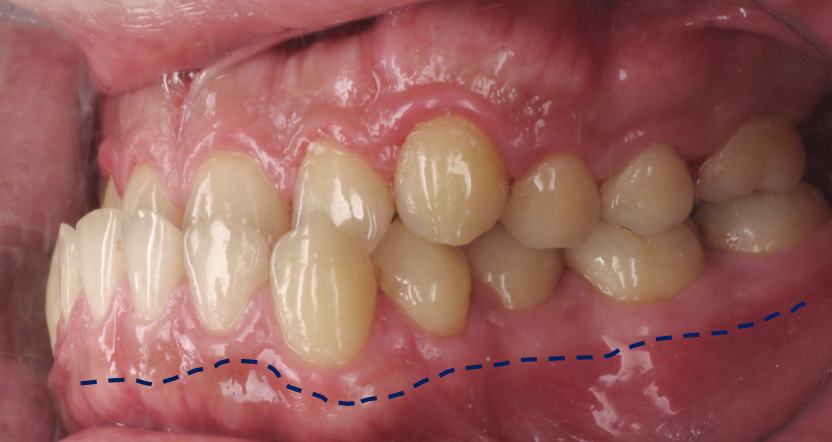

Dehiscence & Fenestration

區分上下顎

- 下顎Cortical plate 厚,越後面越厚

下臼齒

- alveolar process 厚

- 6, 7, 8有 Oblique line

- 6, 7 多牙根一前一後,distal 可能多個